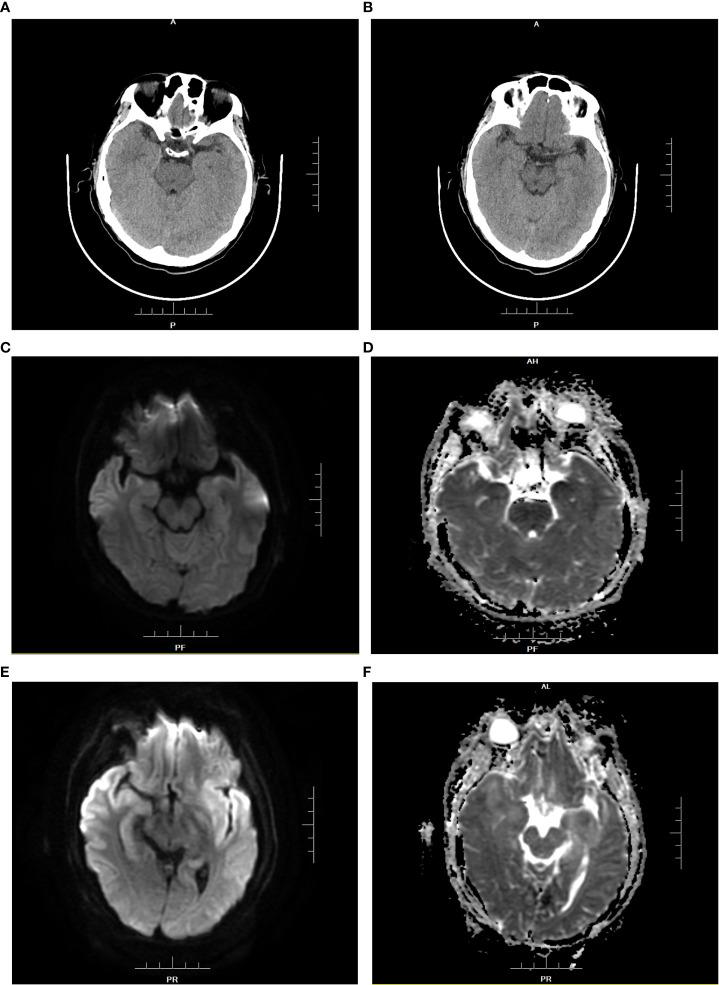

Central nervous system (CNS) infections in adults are rare because of normal immunity and the existence of the blood brain barrier, which prevents the invasion of pathogenic microorganisms. Liver transplant recipients are at an increased risk of opportunistic infections (OI) due to immunosuppressive therapy compared to those with normal immunity. Early diagnosis and timely implementation of treatment are critical for the successful treatment of these infections. We present two cases of intracerebral OI after orthotopic liver transplantation (OLT), with different clinical presentations. Patient 1 presented with epileptic seizures, mainly manifested as unresponsiveness, unconsciousness, and coma complicated with involuntary limb twitching. Patient 2 presented with a consciousness disorder, mainly manifested as unclear consciousness content, poor orientation, calculation power, and logical ability. Next-generation sequencing (NGS) examination of the cerebrospinal fluid confirmed human herpesvirus 6 B (HHV-6B) infection in patient 1 and intracranial Aspergillus infection in patient 2. Intracranial OI has insidious onset and atypical clinical manifestations. NGS can allow for the proper diagnosis and monitoring of the effects of treatment.

成人中枢神经系统(CNS)感染较为罕见,这是因为人体具有正常的免疫功能和血脑屏障,后者可阻止致病微生物的侵袭。与具有正常免疫功能的人群相比,肝移植受者由于免疫抑制治疗而面临更高的机会性感染(OI)风险。早期诊断和及时实施治疗对于成功治疗这些感染至关重要。我们报告了两例肝移植后颅内 OI 病例,其临床表现不同。患者 1 表现为癫痫发作,主要表现为反应迟钝、意识不清和昏迷,伴有不自主的肢体抽搐。患者 2 表现为意识障碍,主要表现为意识内容不清、定向力差、计算力和逻辑能力差。对脑脊液进行下一代测序(NGS)检查后,患者 1 被确诊为人疱疹病毒 6B(HHV-6B)感染,患者 2 被确诊为颅内曲霉菌感染。颅内 OI 的发病隐匿,临床表现不典型。NGS 可实现正确诊断和治疗效果监测。